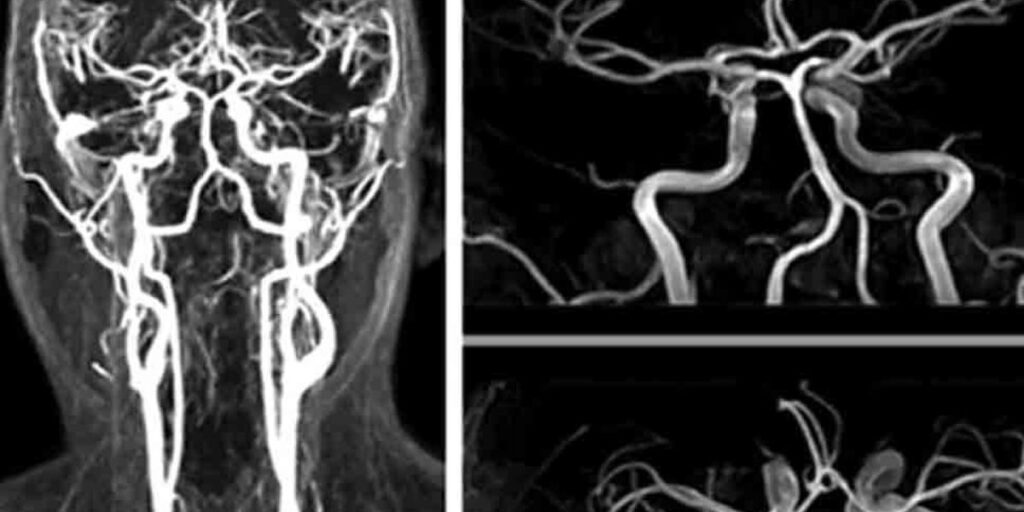

L’Esame Angio RM, o “Angiografia con Risonanza Magnetica”, è una tecnica di imaging medico avanzato che permette di osservare i vasi sanguigni in dettaglio senza l’impiego di radiazioni ionizzanti. A differenza di altre tecniche diagnostiche come la TC o l’angiografia tradizionale, l’Angio RM utilizza campi magnetici e onde radio per ottenere immagini tridimensionali dei vasi, garantendo una valutazione accurata delle condizioni vascolari.

L’Angio RM si avvale di un campo magnetico potente e, in alcuni casi, dell’utilizzo di un mezzo di contrasto a base di gadolinio, somministrato per via endovenosa. Questo mezzo di contrasto rende più visibili i vasi sanguigni, migliorando la qualità delle immagini. Una volta che il paziente viene posizionato all’interno della macchina a risonanza magnetica, le onde radio interagiscono con gli atomi presenti nel corpo, generando segnali che vengono trasformati in immagini ad alta risoluzione. Al Poliambulatorio S-Medical Group di Sora, queste immagini sono fondamentali per la diagnosi accurata di patologie vascolari.

L’Esame Angio RM è indicato per una vasta gamma di condizioni cliniche. Tra le sue principali applicazioni troviamo la valutazione delle stenosi vascolari, degli aneurismi, delle malformazioni artero-venose e dell’aterosclerosi. Grazie a questa metodica, i professionisti sanitari del Poliambulatorio S-Medical Group di Sora possono monitorare il flusso sanguigno e rilevare qualsiasi ostruzione o anomalia, facilitando un intervento tempestivo.

L’Esame Angio RM permette di ottenere immagini dettagliate dei vasi sanguigni, evidenziando stenosi, dilatazioni anomale, aneurismi e altre malformazioni. Questa tecnica diagnostica consente di pianificare in maniera mirata i trattamenti più adeguati, migliorando le prospettive terapeutiche per i pazienti. Presso il Poliambulatorio S-Medical Group di Sora, l’Angio RM è ampiamente utilizzata per diagnosticare condizioni vascolari complesse e per monitorare l’efficacia dei trattamenti in corso.

• Angio RM cerebrale: permette di visualizzare i vasi del cervello e rilevare aneurismi o malformazioni artero-venose.